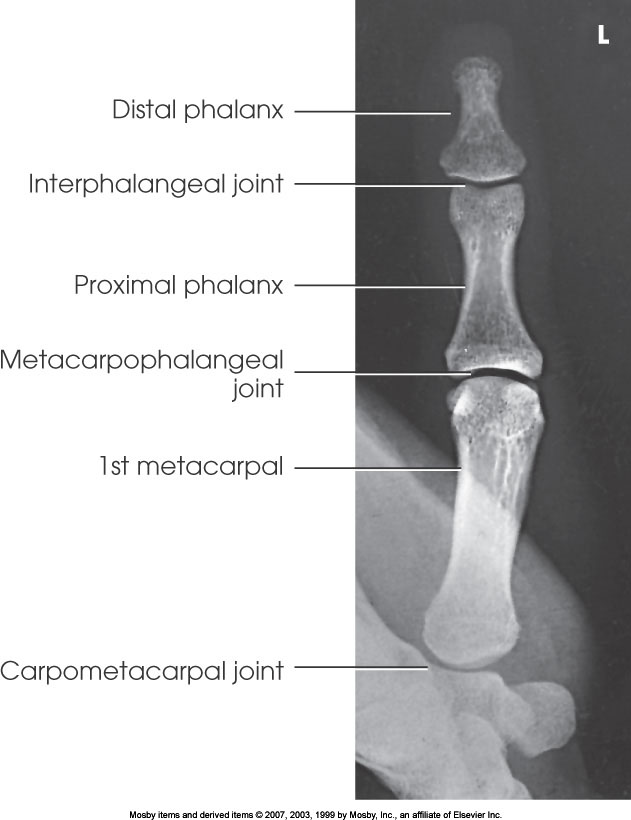

AP Thumb

What position is demonstrated?